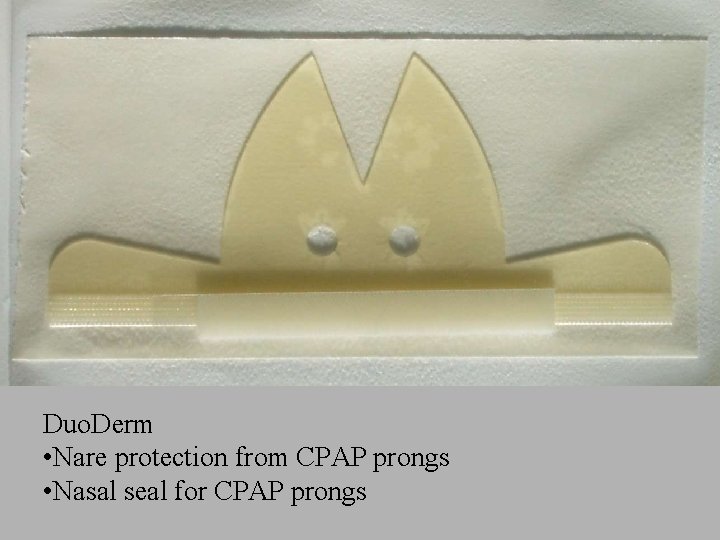

Duo. Derm • Nare protection from CPAP prongs • Nasal seal for CPAP prongs